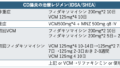

髄液 VZV-DNA PCRが陽性となればそれまでですが、感度が低い(最初の2週間が検出しやすい、既報では感度30%)ということが問題であり、髄液VZV-IgG index(血清IgG/髄液IgG)が有用とされています。PCRとIgGが両方陰性であれば除外できるとされています。